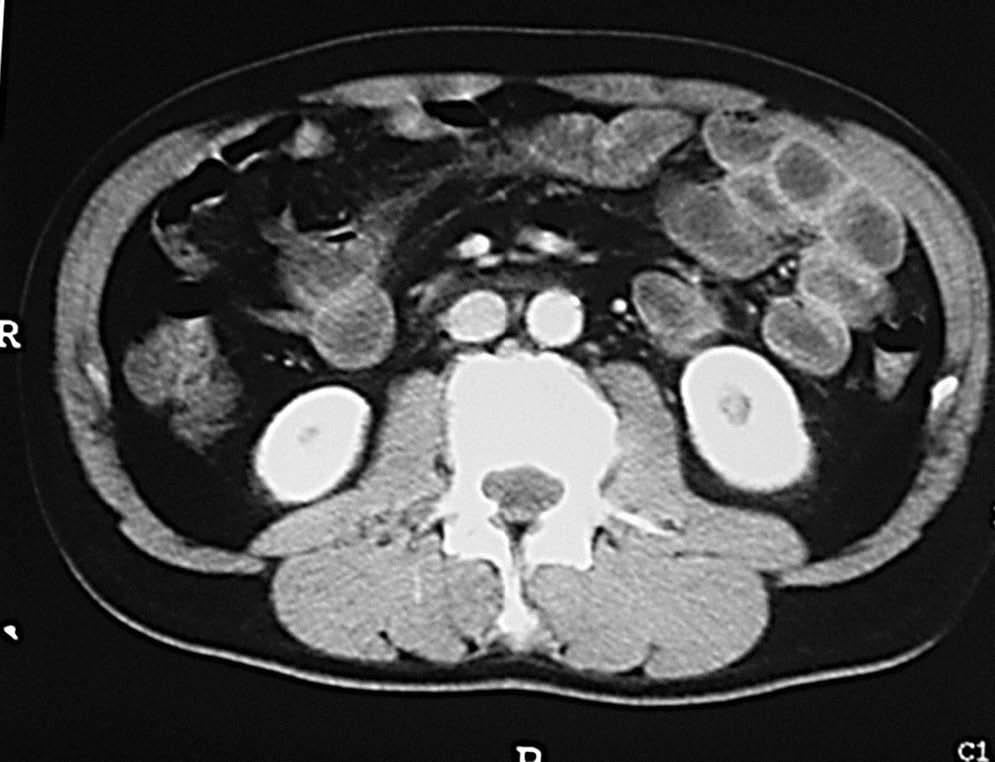

Desde el punto de vista tomodensitométrico (fig. 12) y de la RM los criterios semiológicos son más o menos similares: el engrosamiento mural y la hiperemia característica de una situación inflamatoria activa. Se describe el hecho de que el engrosamiento mural del colon suele ser más marcado en la colitis granulomatosa que en la ulcerosa, lo mismo que la irregularidad de los contornos, que suele ser también más acentuada en los casos de colitis granulomatosa.

Fig. 12.--Enfermedad de Crohn. A) La tomografía computarizada (TC) muestra la afectación del colon de carácter segmentario.(B) En la reconstrucción en plano coronal (MPR) puede apreciarse el marcado engrosamiento mural del colon descendente.